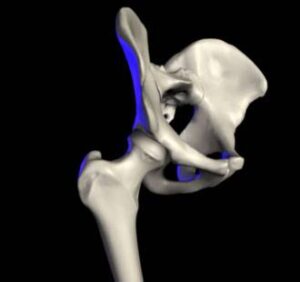

Die Orthopädie ist ein medizinisches Fachgebiet, das sich mit der Prävention, Diagnose und Behandlung von Erkrankungen und Verletzungen des Bewegungsapparates beschäftigt. Knochen, Gelenke, Muskeln, Sehnen und Bänder müssen gemeinsam funktionieren, um uns Beweglichkeit und Stabilität zu ermöglichen.

Auf unserer Seite finden Sie umfangreiche Informationen zu orthopädischen Beschwerden und Erkrankungen. Von der Arthrose über Bandscheibenvorfälle bis hin zu Kreuzbandriss und weiteren Sportverletzungen: wir geben Ihnen einen Überblick über die häufigsten orthopädischen Krankheitsbilder, wie sie behandelt werden können und inwieweit ein Bildgebungsverfahren, wie eine (z.B. MRT Knie, Rücken MRT) bei der Diagnose bei der Diagnose unterstützend wirken können.